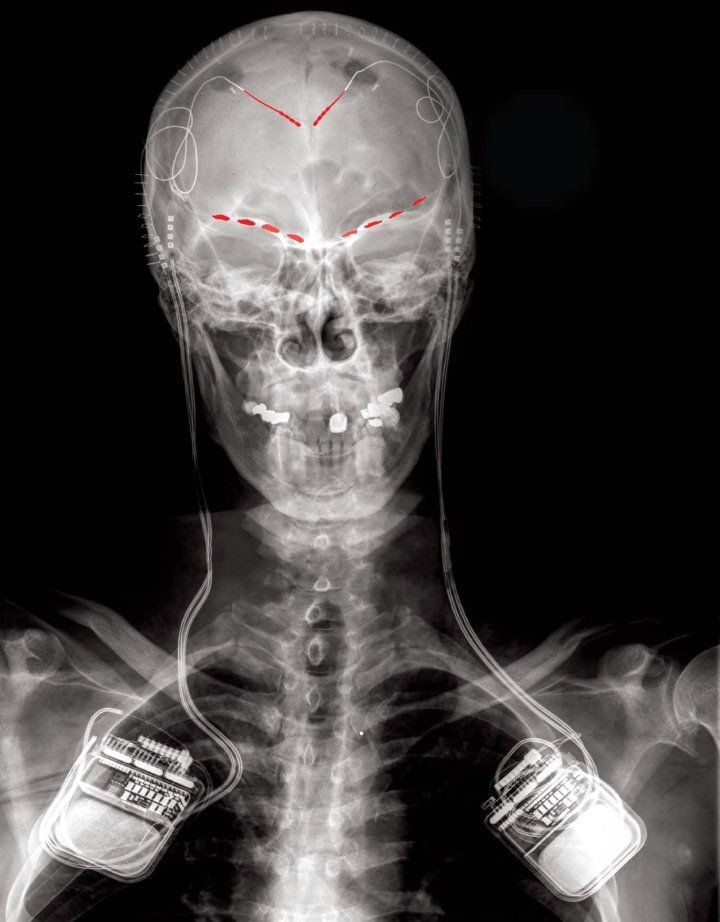

Immagine frontale a raggi X di un partecipante allo studio che mostra elettrodi di registrazione del cervello impiantati (in rosso) collegati a un impianto bidirezionale di stimolazione e registrazione del cervello su entrambi i lati del corpo. Immagine di Prasad Shirvalkar